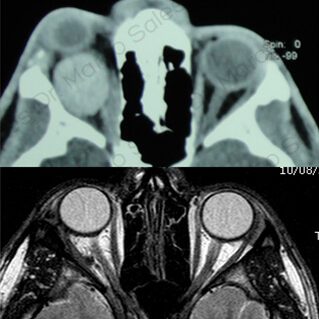

ÓRBITA

ORBITOPATÍA TIROIDEA